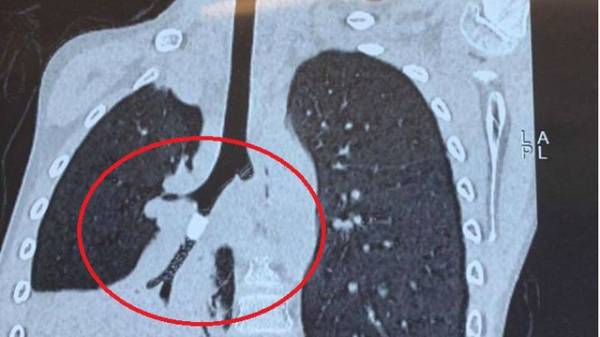

Tuy nhiên, qua quá trình hội chẩn, bác sĩ chú ý đến vùng bẫy không khí trong phim chụp X-quang phổi. Khi kết hợp với phim CT-scan ngực cho thấy có sự hiện diện của một vật thể lạ trong phế quản, dạng hình trụ, bít lòng hoàn toàn nhánh phế quản dẫn tới việc không khí không thể đi qua hoàn toàn vật thể, gây tắc và xẹp toàn bộ nửa phổi phải.

Bệnh nhi đã được soi phế quản và gắp ra được mẩu nhựa cứng khô. Theo bác sĩ, dị vật làm cho phế quản phù nề, viêm trợt do bị chèn ép. Phim chụp X-quang ngực sau đó cho thấy dấu hiệu thông khí phổi tốt, tình trạng xẹp phổi phải đã được giải quyết triệt để.